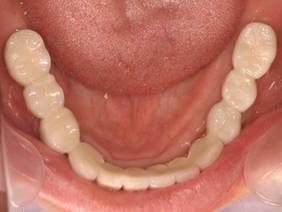

上部構造装着後6年。ハイブリッドレジンを使用したため、少し艶がなくなってきました。上部構造の材料には金属、ハイブリッドレジン、セラミックなどがあります。セラミックはきれいですが欠けやすいため、最近はフルジルコニアを使っています。

上顎 少しすり減ってきました。

下顎。12か月に一度メインテナンスをしています。

インプラント装着後6年。順調に経過しています。12か月毎のメインテナンスをしています。